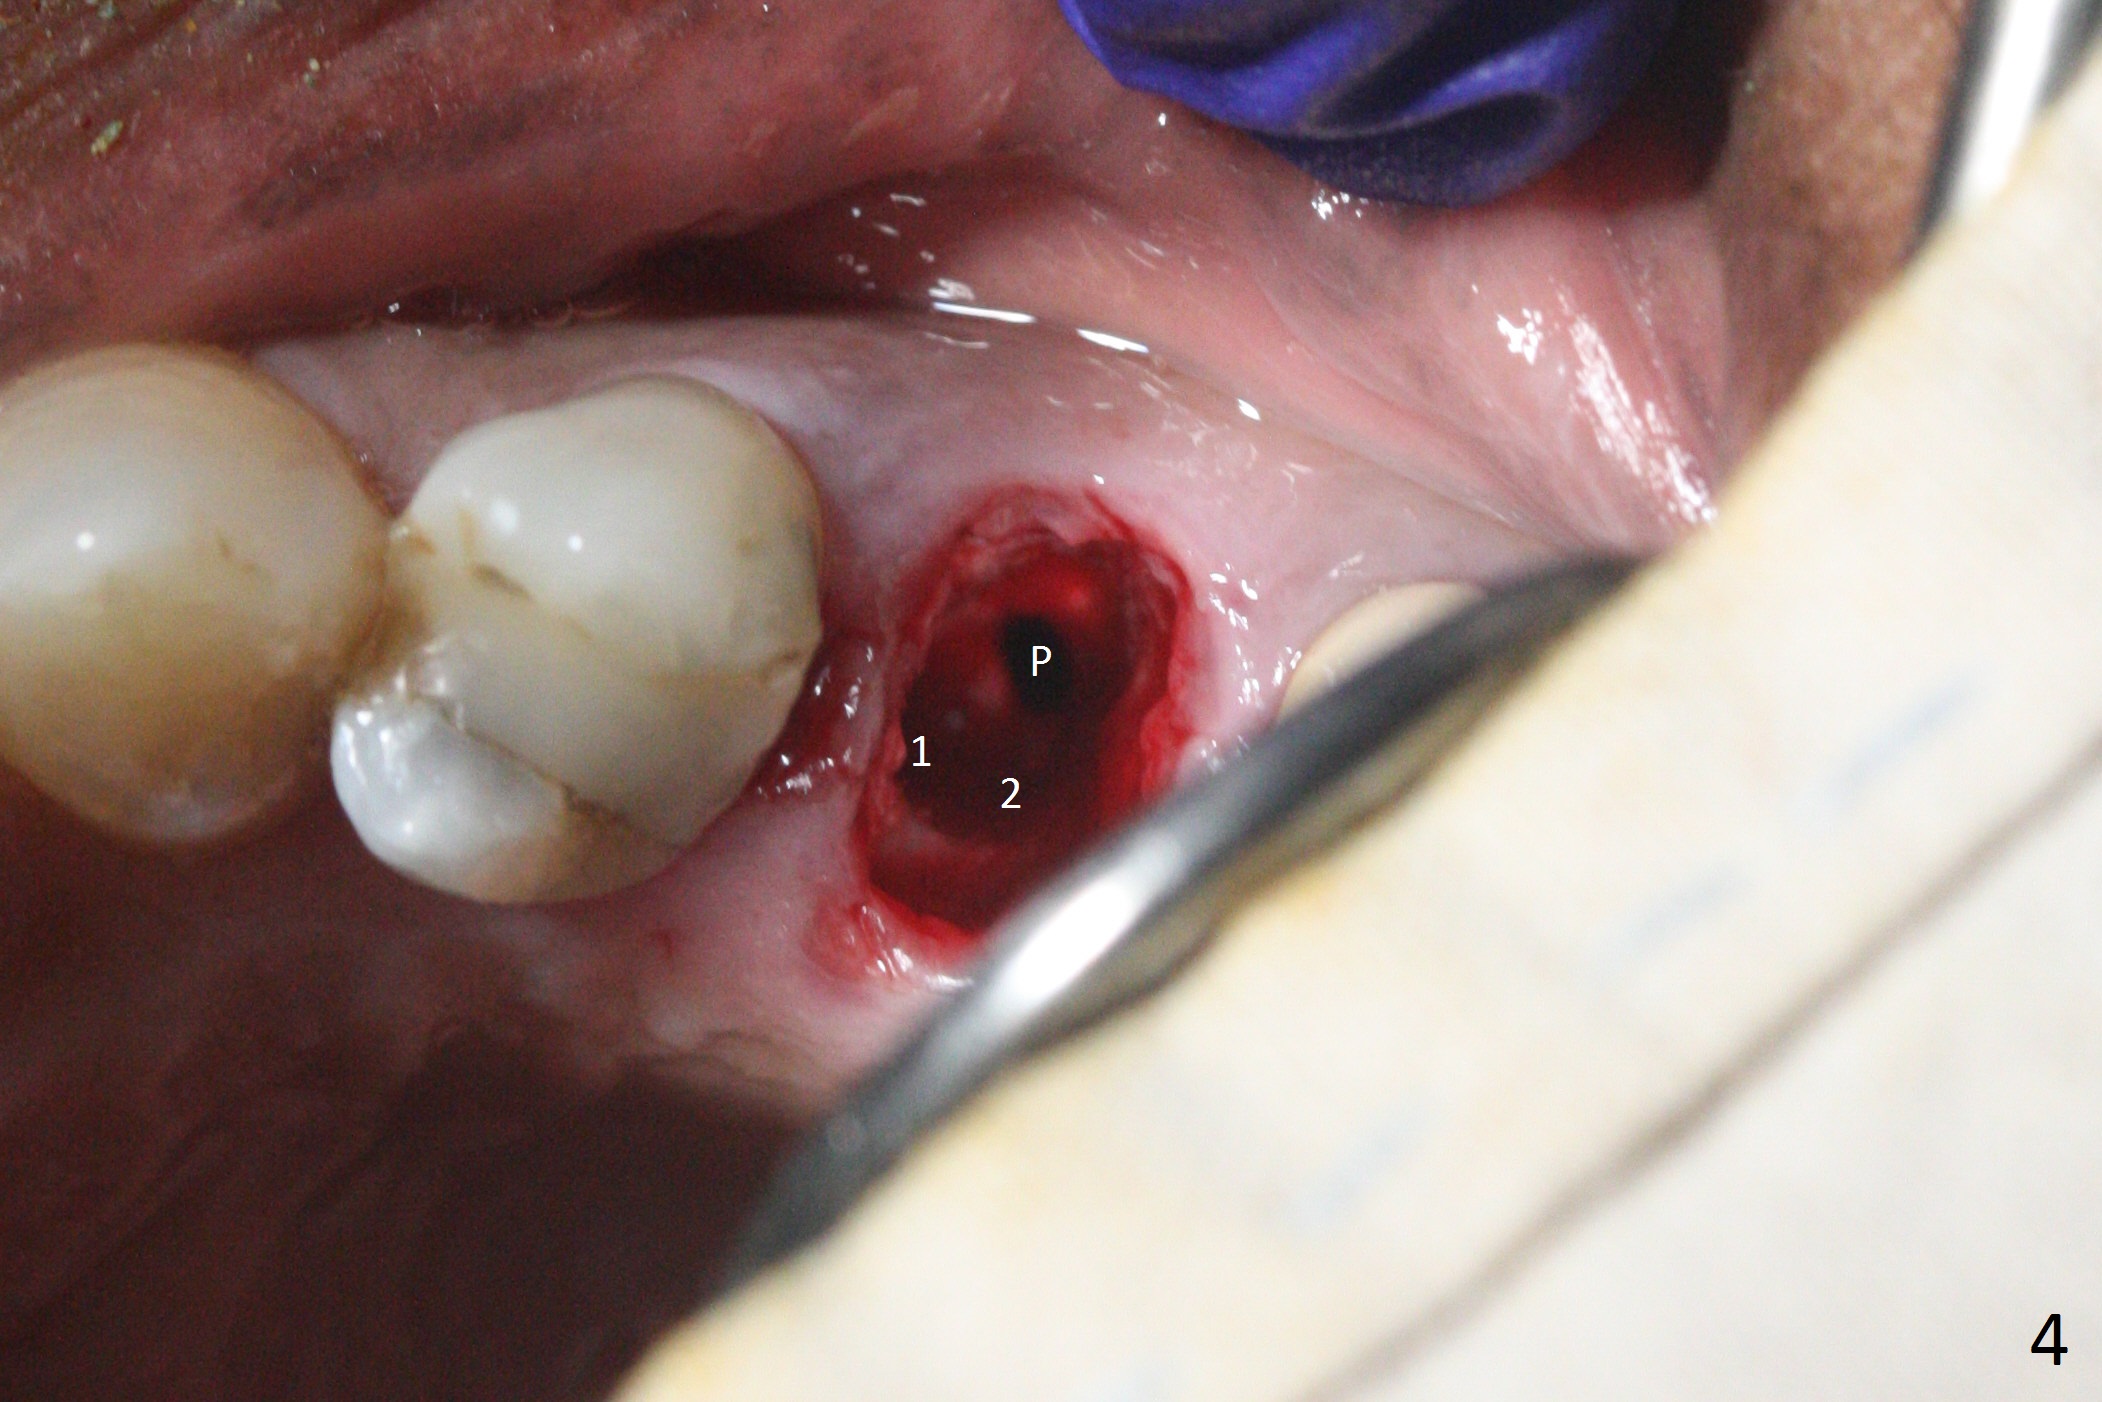

Since the apical native bone is limited at #13 after extraction, no PA is taken until a 4x11 mm dummy implant is placed after 1.6 mm and 3.3 mm drills for 13 mm (Fig.1). After using Lindamann bur to move the osteotomy distal and reusing 3.3 mm drill, the trajectory of a 4.5x11 mm IBS dummy implant improves (Fig.2,3 with low stability). When the implant is removed, the buccal portion of the socket is found to be perforated (Fig.4 P). Although the reason for the perforation is unknown, it is repaired by insertion of a piece of PRF plug, followed by allograft. #1 and 2 in Fig.4 represent the 1st and 2nd osteotomies, as shown in Fig.1 and 2, respectively. The trajectory of the final 5x13 mm implant is acceptable (Fig.5-7, different angulations), so is insertion torque (45 Ncm). After placing a 5.5x4(4) mm abutment, an immediate provisional is fabricated (Fig.8 P) with occlusal clearance (*). The interdental papillae remain in place 12 days postop (Fig.9 *). There is no sign of postop sinus infection. The provisional is loose 18 days postop; the abutment is changed to 5x4(3) mm (Fig.10). It is difficult to catch the mesial margin of the abutment for impression 4 months postop, due to poor oral hygiene and the short cuff (3 mm, Fig.11). The appointment for impression is rescheduled with emphasis on oral hygiene and no wearing the provisional for a few days prior to next appointment. Bone has grown into the space between the 1st and 2nd threads 5 months post cementation (Fig.12) and the bone is normal, solid and dense 2 years 11 months post cementation (Fig.13 >). There is mesial open margin of the tooth #14 (Fig.13,14 *).